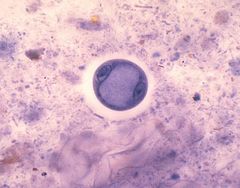

Entamoeba coli cyst | |

إنتاميبا كولاي هي أحد أنواع الأميبا الطفيلية (إنتاميبا)، وتتوجد في الجزء العلوي من الأمعاء الغليظة للإنسان وتتغذى على البكتيريا وبقايا المواد الغذائية ولا تسبب ضررا بل أنها قد تكون نافعة بسبب تغذيتها على البكتيريا. ومثل هذه العلاقة بين الطفيل والعائل تعرف بالمعاشرة الغذائية (Commensalism) وإذا خرجت مع البراز تموت ولذلك تفرز حول نفسها غلافا صلبا (حوصلة) تنقسم النواة داخله إلى 8 وتبقى الحوصلة حية ما دامت في وسط رطب حتى إذا ما وصلت إلى أمعاء عائل جديد عاد للحياة فيذوب الغلاف وتخرج منه وتنقسم إلى ثمانية أفراد.